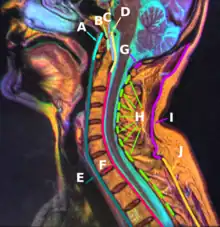

The nuchal ligament is a ligament at the back of the neck that is continuous with the supraspinous ligament.

The nuchal ligament extends from the external occipital protuberance on the skull and median nuchal line to the spinous process of the seventh cervical vertebra in the lower part of the neck.[1]

From the anterior border of the nuchal ligament, a fibrous lamina is given off. This is attached to the posterior tubercle of the atlas, and to the spinous processes of the cervical vertebrae, and forms a septum between the muscles on either side of the neck.

I: Nuchal ligament